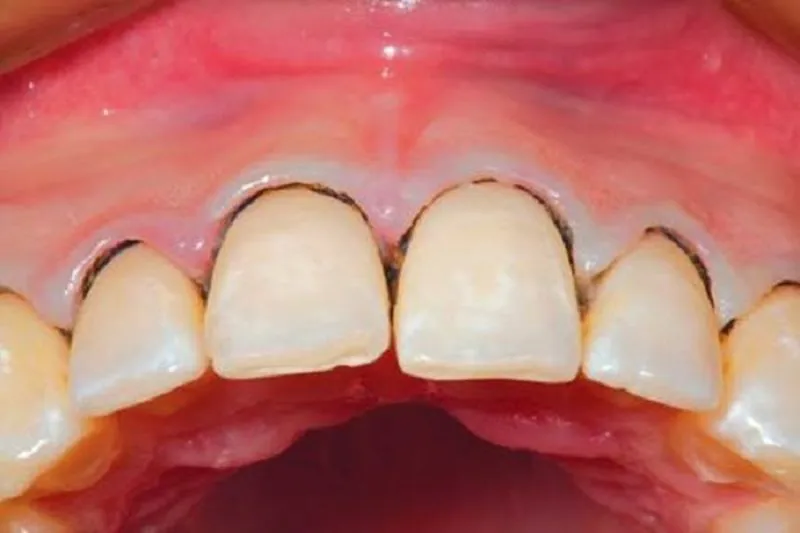

Viêm nướu răng sứ

Viêm nướu

Khoảng 90% người lớn bị viêm nướu do mảng bám vi khuẩn tích tụ trên bề mặt răng. Dấu hiệu của viêm nướu bao gồm: nướu đỏ và viêm sưng, có chảy máu trong khi đánh răng, răng không lung lay. Viêm nướu không gây tổn thương không thể khắc phục đối với xương hoặc mô xung quanh. Nhưng nếu không được điều trị có thể tiến triển thành viêm nha chu.